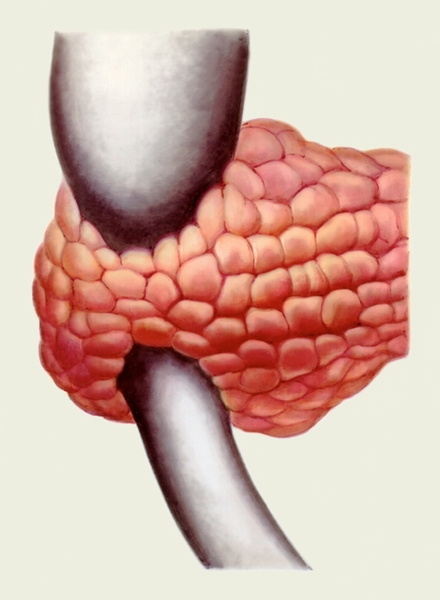

УЗИ диагностика кольцевидной поджелудочной железы: что важно знать